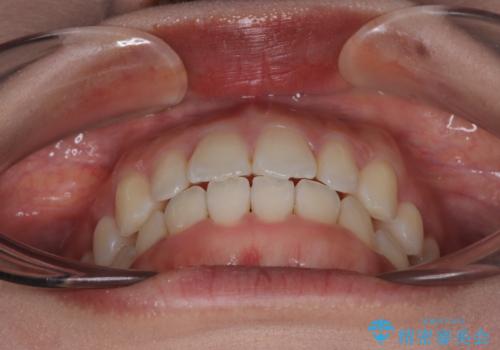

治療終了時

前歯が自然なアーチにきれいに並び、正中(上下の中心線)も整い、咬み合わせも良好です。

側方拡大することで、非抜歯であるにも関わらず前歯が前方に出ることなく、バランスの良い仕上がりとなりました。